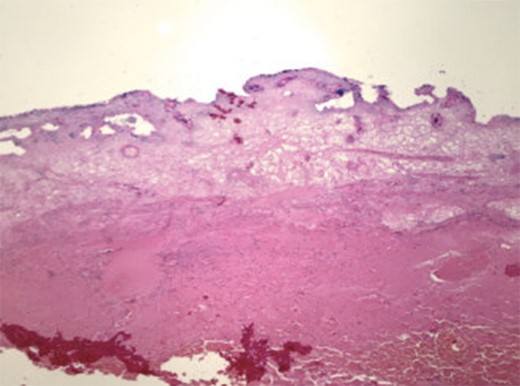

A 77-year-old female presented with acute right upper quadrant (RUQ) pain with associated nausea for 12 hours. Pain was described as dull and more severe after eating. The patient had prior episodes of this pain, occurring for the last several years. She admitted weight loss and denied any fevers, chills or vomiting. Medical history included hypothyroidism, hyperlipidemia, malabsorption problem for which she takes B12 and folic acid supplements. Surgical history included appendectomy. She denied any tobacco or alcohol use. Abdominal exam demonstrated a soft, non-distended abdomen with a palpable mass in the RUQ, RUQ tenderness to palpation without rebound or guarding. Lab values were significant for an elevated leukocytosis; chemistry and hepatic function panel within normal limits. CT scan demonstrated a distended hydropic appearing gallbladder with pericholecystic fluid and wall edema without evidence of gallstones (Fig. 1) and a common bile duct of 9 mm. Subsequent RUQ ultrasound revealed a dilated gallbladder with a thickened wall and a small amount of pericholecystic fluid, suggestive of acalculus cholecystitis. The patient was admitted, started on Cefepime and Flagyl, and scheduled for a laparoscopic cholecystectomy. Upon entering the abdomen, a large necrotic, gangrenous appearing gallbladder was noted (Fig. 2a–d). It had maneuvered itself over the top of the liver and completely necrosed its base. The gallbladder was extremely distended, encompassing much of the patient’s RUQ. The common bile duct was able to be identified. The gallbladder was not detorsed due to risk of toxin release into circulation as the gallbladder was gangrenous. Decompression of the gallbladder was not attempted due to concern for a possible malignancy. A 12 mm trocar was placed in the RLQ and a GIA stapler with Peristrips was used to completely transect the base of the gallbladder, including the cystic artery and duct. The gallbladder was placed in a large EndoCatch bag and the umbilical incision was extended to remove it from the abdomen. Hemostasis was achieved at the staple line and no other evidence of abnormalities were noted. The patient tolerated the procedure well. The patient had an uncomplicated postoperative course. Her postoperative hepatic function panel remained within normal limits. Histopathology was consistent with acute cholecystitis with gallbladder hemorrhage and necrosis (Fig. 3).

Histopathology revealed acute cholecystitis with hemorrhage and necrosis of the gallbladder.